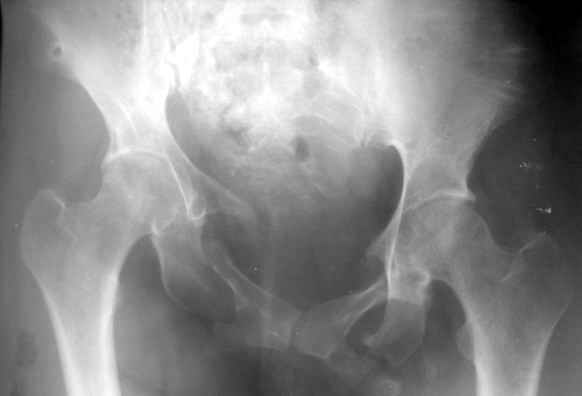

Вопрос Уральскому Пельвиоцентру: через год после травмы, довольно симпатичная женщина, болей нет, только ходит призрамывая на правую ногу и сидит криво, мышечная ассиметрия практически не выражена, хотя слабость справа есть. Легко компенсируется подкладкой стельки 1,5 см с выраженным клиническим эффектом. Посылаю снимки с вопросом - можно ли устранить деформацию в Вашем аппарате, если можно - то поподробнее. Снимки с разницей во времени почти 1 год. Жду ответа как соловей лета. ЛАФ.

У нас в отделении даже куда менее значительные деформации считаются показанием к устранению, тут, конечно, надо постараться улучшить форму.

Для уточнения объема и характера операции надо доснять inlet/outlet проекции и сделать КТ переднего и заднего отделов. Надо уточнить, делать ли остеотомии, или нет сращения и можно закрыто аппаратом разорвать. Ну а схему аппарата ты видел, если ве-таки ее надо, завтра заброшу, если Рунков или Шлыков раньше сами не ответят.

Дело в том, что там непревильно сросшийся перелом боковых масс крестца - Делать ли остетомию - продолженную репозиуию в аппарате, внутреннюю фиксацию переднего и заднего полукольца или вместо всего этого одномоментно удлинить бедро на 1,5 см, в крайнем случае добавить резекцию седалищного бугра слева - прямее будет сидеть.? ЛАФ.

Привет! Случай типичный при такой травме, когда накладывают переднюю раму аппарата, но репозиции не достигают и игнорируют повреждение задних отделов. Интересно узнать всю историю поподробнее, где и как лечилась, сроки, была ли информация у больной, что ей можно было помочь гораздо раньше и с большим эффектом.

На счет жалоб: к году полутора при этом повреждении больные приспосабливаются к новым условиям и активно предъявляют жалобы, как правило, только на боли, с которыми они смирились и хромоту. Перелом боковой массы крестца или срастается или образует достаточно спаек для стабилизации повреждения в отличие от чистых разрывов КП сочленения.

Однако при расспросе картина становится более ясной, т.к. выявляются ограничения в ходьбе, сидении, лежании и способности к труду. Мы пользуемся универсальными шкалами, хорошо бы узнать ее баллы по Majeed. Для уточнения диагноза и степени сращения необходимы дополнительные проекции inlet, outlet и обязательно КТ таза с шагом 0,5мм. Не плохо было бы и общий вид узреть - фас, сзади и стоя на одной ноге.

Объем хирургического пособия зависит от этих данных.

Привожу пример лечения больного с 7 месячной деформацией. Отеотомии - аппарат - внутренняя фиксация.

Рентгенограммы до и через месяц после окончательной стабилизации. Потом поищу более поздние снимки.